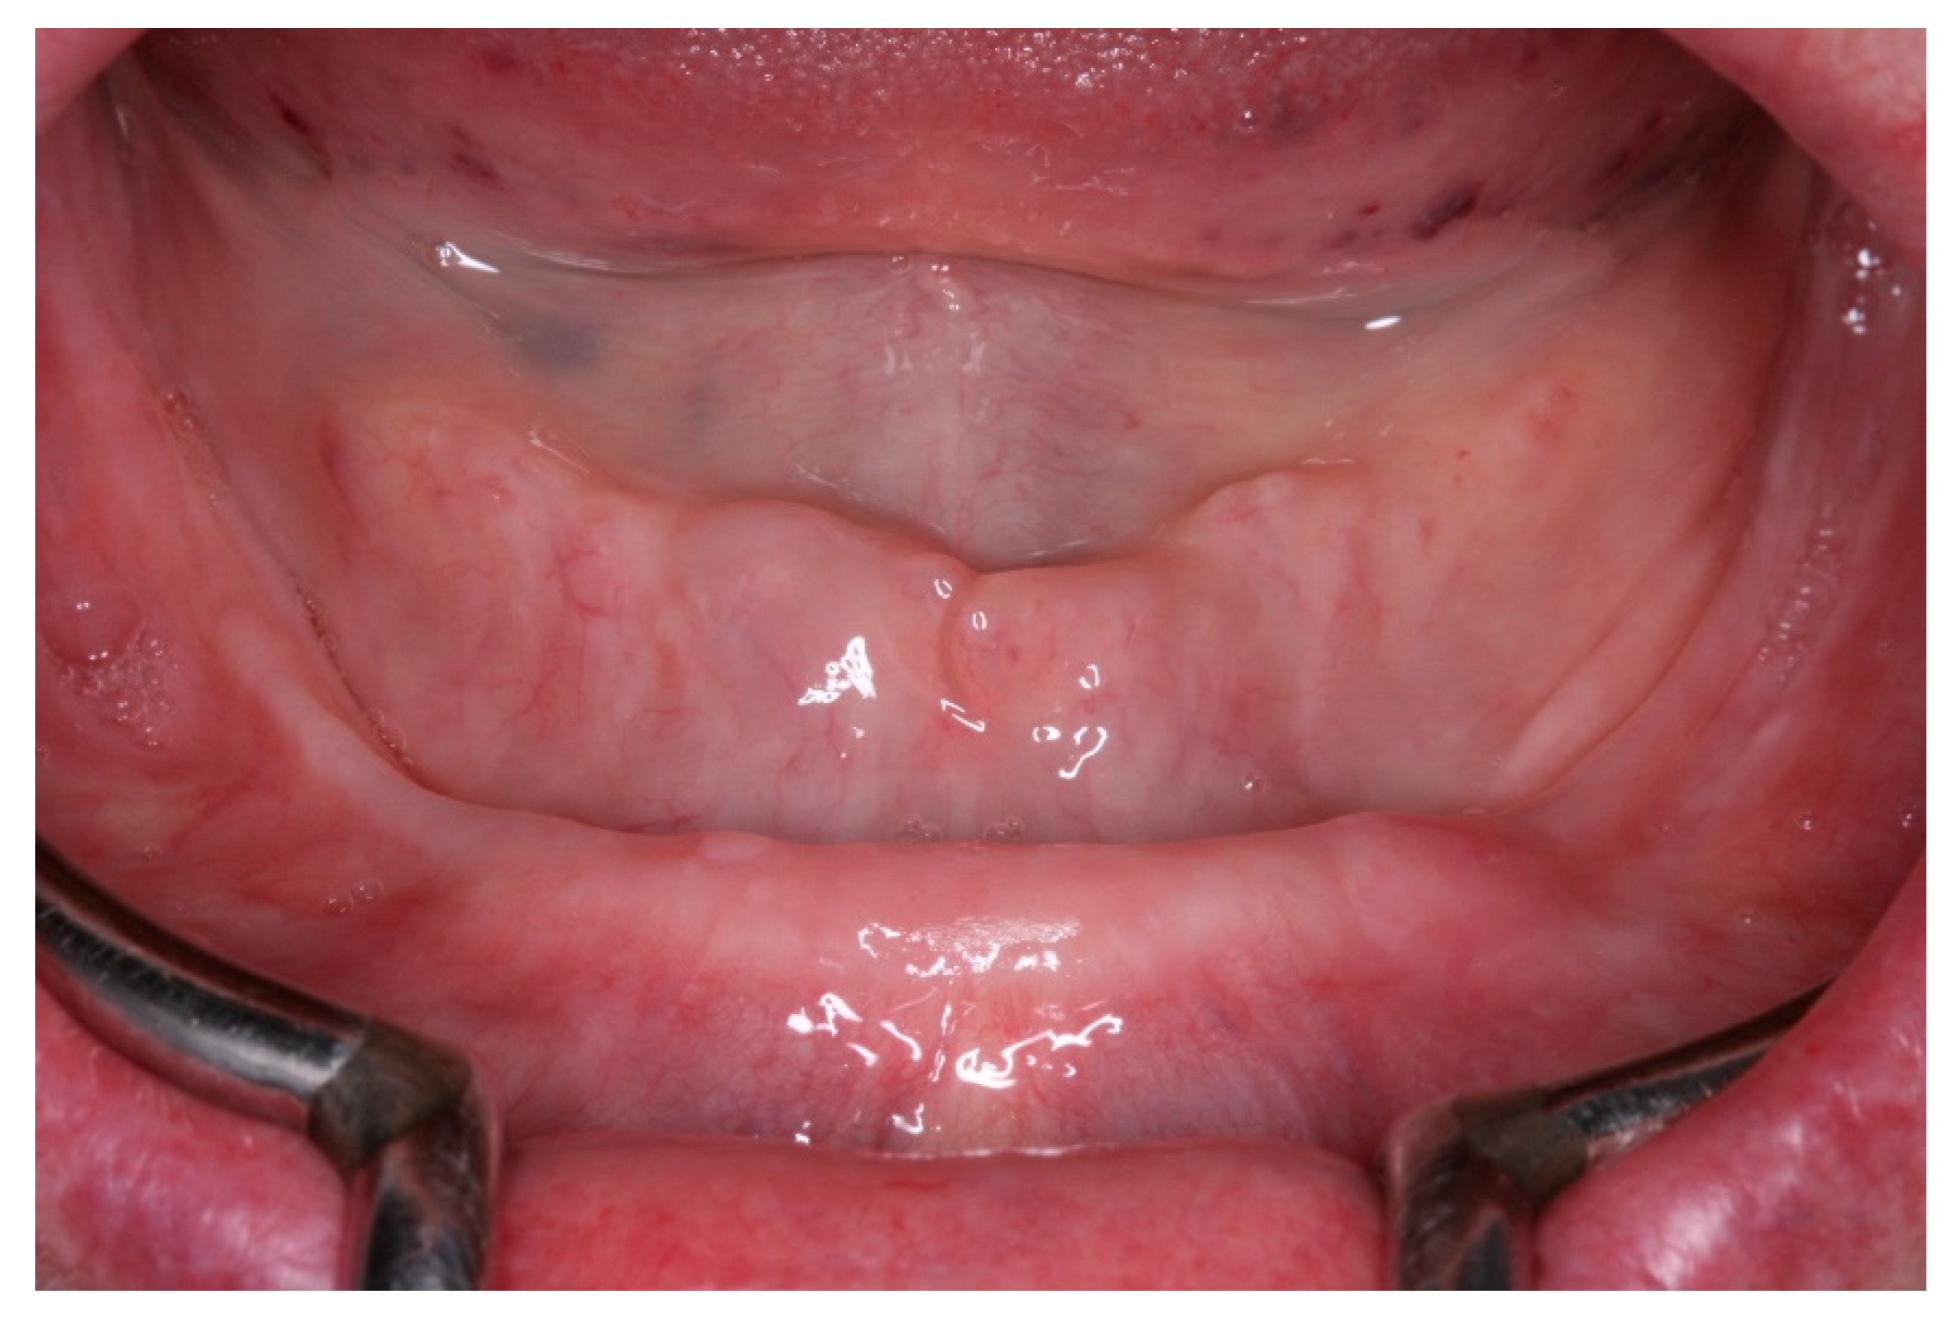

Figure 19. View of the peri-implants mucosa after 3 months of healing.

After a healing period of 3 months the patient returned to change que temporary fixed prothesis for a new one, more delicate and with a reinforced metallic bar for a better ferulization of the implants and better dissipation of the stress during function. After removal of the temporary prosthesis we could see the peri-implant mucosa was healthy (Figure 19), without bleeding on probe nor peri-implant sulcus with more than 3mm depth, even around the implants were there were lack of a satisfactory keratinized tissue band, showing us that the patient was being able to maintain the cleansing of the region below the prosthesis. A new fixed rehabilitation over the implants was produced (Figure 20, Figure 21 and Figure 22). 2 years after the surgery we could see on a control panoramic radiograph no signs of bone remodeling above the expected around the implants (Figure 23).